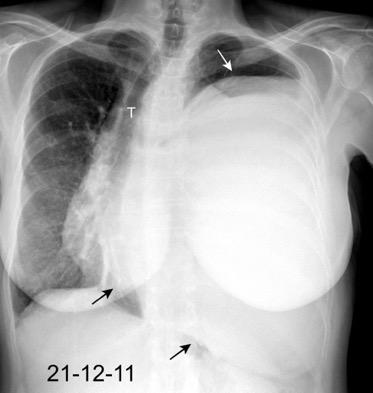

Marzo 2014: Perforación longitudinal distal secundaria a episodio de vómito (síndrome de Boerhaave). Derrame pleural izdo. que evoluciona a empiema.

Wang C-T et al. Tension hydropneumothorax in a Boerhaave syndrome patient: A case report . World J Emerg Med, 2021. Katabathina V et al. Nonvascular, nontraumatic mediastinal emergencies in adults:a comprehensive review of imaging findings. Radiographics. 2011.